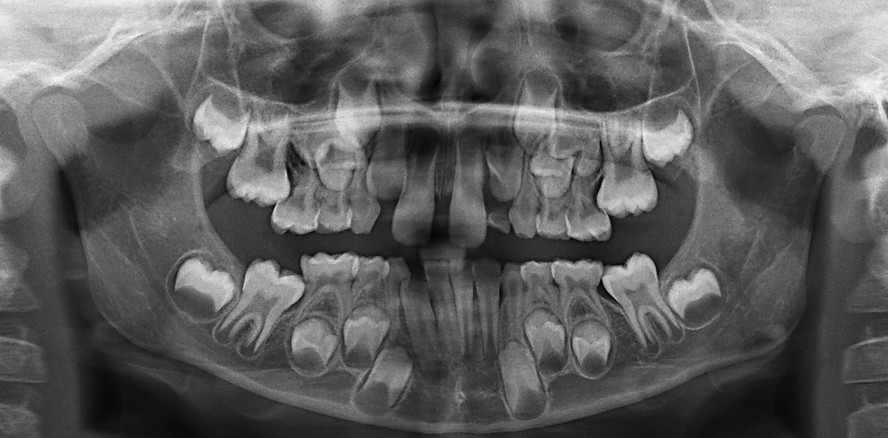

Der Besonderheit der unterminierenden Resorption, meist der Milchfünfer durch die bleibenden 6er (Abb. 5) oder der Milchzweier durch die bleibenden 1er (Abb. 6 – mit häufiger Folge, dass die bleibenden 2er dann die Milchdreier resorbieren), sollte auch Beachtung geschenkt werden. Beides steht für ein Mangelwachstum der Kiefer und sollte frühzeitig therapiert werden, um die spätere Extraktion von bleibenden Zähnen zu verhindern.